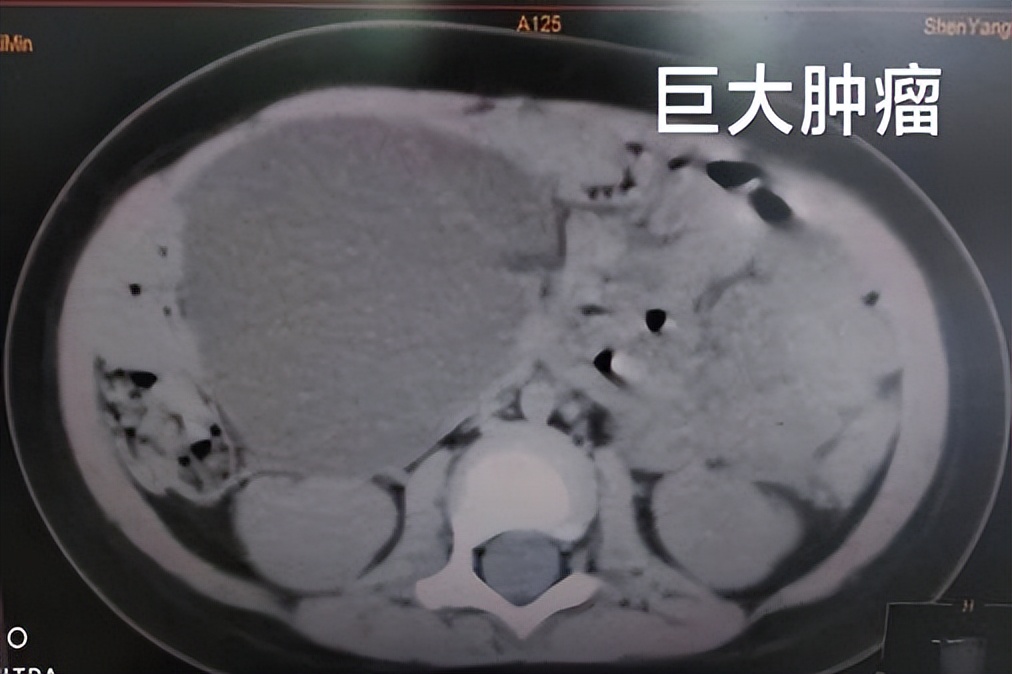

经过系统检查后,确定了敏敏的肿物来源于右侧盆腔,与卵巢关系密切,是典型的“畸胎瘤”影像学改变,并且根据超声科主任会诊结果进一步明确了肿物来源于左侧卵巢,且左侧卵巢已无正常结构,符合左侧卵巢来源畸胎瘤,手术势在必行!为制定完善的手术方案,曲主任立即邀请超声科、放射科、手术麻醉科、输血科等相关科室专家讨论病情,汇总手术所需要的所有准备事宜,并特请国家儿童医学中心的著名专家进行远程会诊,结合会诊结果和患儿病情特殊性在术中可能发生的突发状况的应对措施仅用一天时间就制定好了所有方案,这个手术既要确保肿瘤的完整切除,也要尽量保留患侧残余卵巢组织的功能,这是个挑战,但也是我们作为医者的责任与担当。

腹腔镜下左侧卵巢畸胎瘤切除术,这是敏敏即将进行的手术,曲朝晖主任亲自主刀,由于孩子年龄小,肿物体积偏大,需要细致的手法和充分的耐心一点点进行切除和剥离,汗水早就浸透了所有参与手术人员的衣衫,但是没有人动摇,始终保持有序的手术流程,全神贯注的投入其中。最终,经过近四个小时的努力,成功保留了左侧残余卵巢组织,畸胎瘤被完整切除,手术取得圆满成功! 由于是采用微创技术,术后敏敏腹部伤口仅几毫米,随着年龄的增长疤痕几不可见,成年后的生育能力也不受影响,这让敏敏的父母在激动之余对我们的医护人员赞不绝口,感激之情溢于言表!而敏敏在经过几天的抗感染治疗后切口恢复良好,不日即将出院!